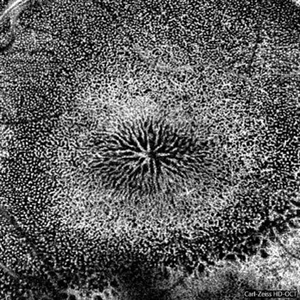

Female patient, 37 years old, Caucasian, with complaint of low lateral stroke in abos the eyes. In the retinal mapping examination and retinography, important alterations in the optic nerve head suggestive of DRUSAS DE PAPILA were observed. After being confirmed in the Autofluorescence examination, we observed Autohyperfluorescence compatible with deposits of calcified hyaline material, as well as another complementary exam such as USG and OCT.

Photographer: JEFFERSON R SOUSA - Study Center and Ophthalmological Research Dr. Andre M V Gomes, Institute Dr. Suel Abujamra, Clinic Marco Antonio Albhy Ophthalmology / São Paulo-Brazil

Imaging device: Heidelberg - HRA Angiograph, Autofluorescence com 30 degrees.

Condition/keywords: calcified drusen, drusen of optic disc